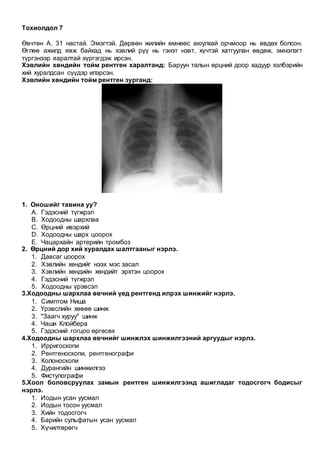

Бодит үзлэгт: хүүхэн хараа 2 талдаа ижил бус, гавлын дотрох цус алдалт гэж сэжиглэн

толгойн компьютерт томографийн шинжилгээ хийсэн.

Компьютерт томографийн зураг:

1. Оношийг тавина уу?

A. Тархины цус харвалт

B. Эпидураль гематома/ экстра-аксиаль гематома

C. Менинангиома

D. Субдураль гематома/ интра-аксиаль гематома

E. Шваннома